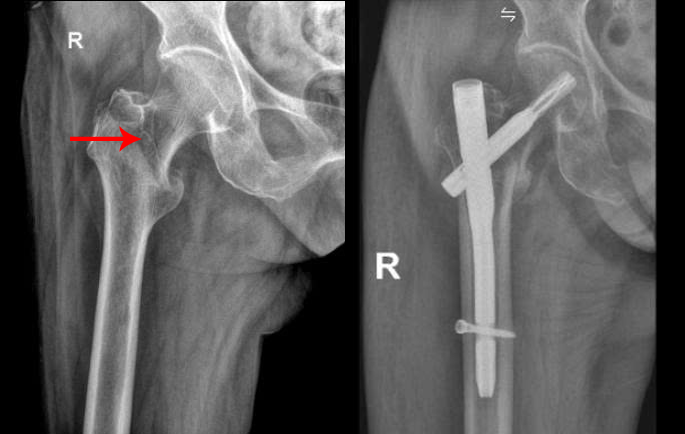

Ms. Loc's intertrochanteric femoral fracture before and after surgery. Photo: Tam Anh General Hospital |

During Ms. Loc's multidisciplinary pre-operative screening, doctors found a coronary artery branch narrowed by 80-90%. They carefully calculated the appropriate anesthesia dosage. The surgical team utilized an orthopedic operating table for reduction and checked the intertrochanteric femoral fracture using an image intensifier screen and a mobile X-ray system (C-arm). This positioned the patient optimally to shorten surgical time.

Within 40 minutes, surgeons made small 2-3 cm incisions outside the fracture site. They performed intramedullary nailing and fixed the intertrochanteric femoral fracture with screws, then closed the incisions. This minimally invasive technique reduced risks during and after surgery, such as blood loss and cardiovascular complications for the patient.